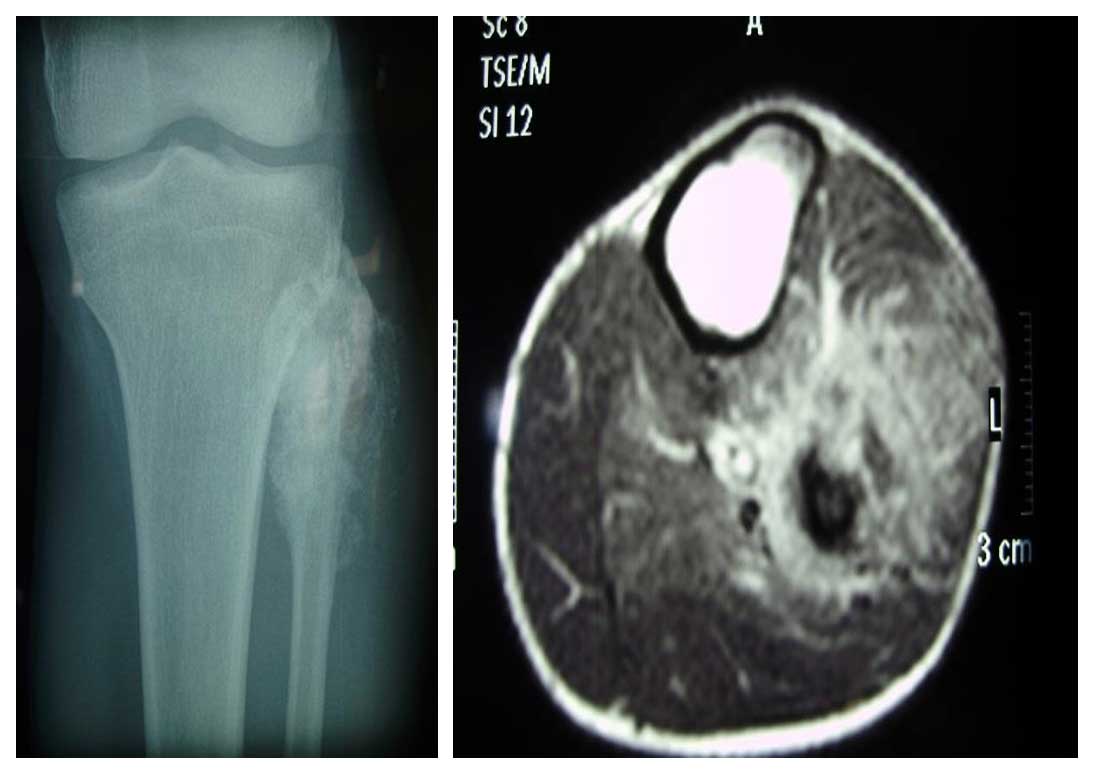

Ameliyat Öncesi: Röntgende proksimal fibulada düzensiz sınırlı sklerotik lezyon, MR’da yumuşak dokuya uzanım gösteren çevreleyen ödemin eşlik ettiği tümör dokusu görülmekte.